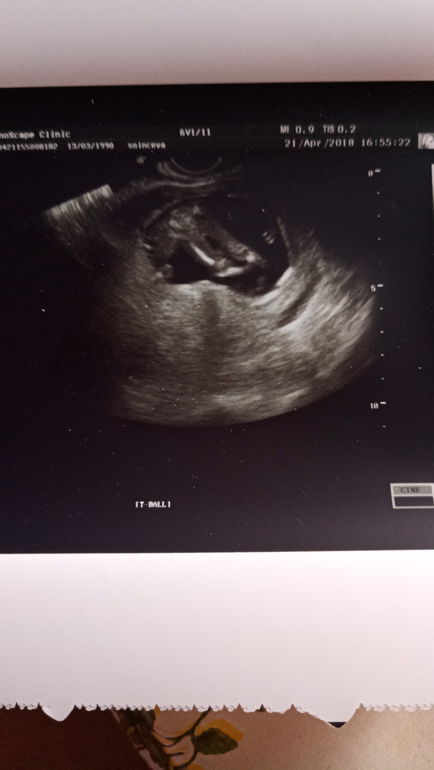

Пол, в 15 недель

Вопросы про УЗИ, обследования и анализы: что, где, как, когда?Девочки, врач сказала 80% девочка, а вы что думаете, по поводу бугорка